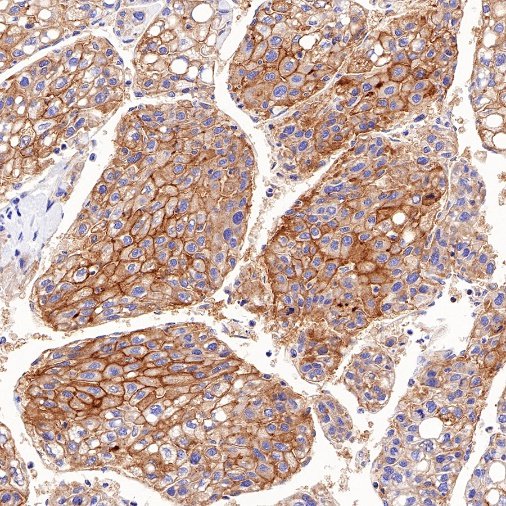

Immunohistochemistry

IHC shows positive staining in paraffin-embedded human kidney. Anti-MDR1/ABCB1 antibody was used at 1/1000 dilution, followed by a HRP Polymer for Mouse & Rabbit IgG (ready to use). Counterstained with hematoxylin. Heat mediated antigen retrieval with Tris/EDTA buffer pH9.0 was performed before commencing with IHC staining protocol.